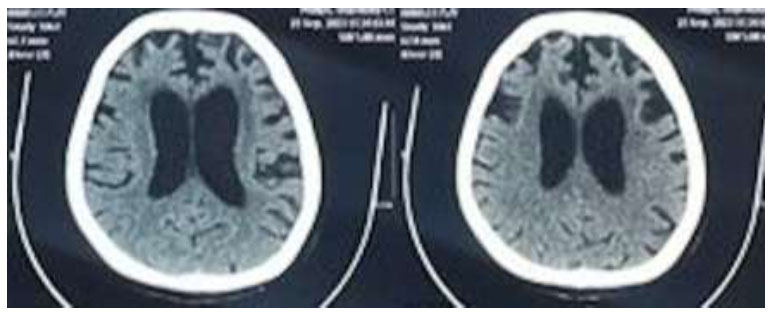

What she was trying to convey was that after waking up, she made her bed to keep it tidy. The patients also showed impaired comprehension. When assessed using TADIR, the patients had impairment in understanding the syntactically complex sentence. For example, for the question “Seorang bayi lebih besar daripada seorang dewasa. Benar atau tidak?” (A baby is bigger than an adult. True or false”), she answered true. In the sentence production test using pictures, she was asked to make a sentence from a picture, but she could only mention the objects and not make a sentence. The imaging results of one nfvPPA patient revealed atrophy in both frontal lobes, with more pronounced atrophy on the left side, as illustrated in Fig. (1).

Imaging result of one nfvPPA patient.

In our study, all patients underwent global cognitive assessment using MoCA-INA, which showed a lower-than-normal score in each patient. This finding is not surprising since it is a verbal-based tool and highly dependent on the patient’s verbal and language ability. We assessed language functions that included sentence production during spontaneous speech, word and sentence compre- hension, repetition, naming, reading, and writing to clinically classify each PPA variant. A key indicator in patients with PPA is the presence of asymmetrical damage to the cerebral hemisphere that is dominant for language function, manifesting as cortical atrophy, hypoperfusion, or hypometabolism. This illustrates the selective partial vulnerability of specific networks to neurodegenerative diseases [10]. Our study found the area of atrophy correlated well with the area known for each variant, namely left frontal in nfvPPA, left anterior temporal in svPPA, and left temporoparietal in lvPPA [3, 15].